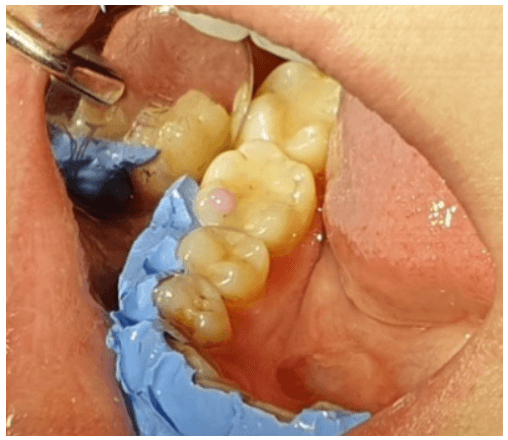

iii. In the third session, a layer of purple coloured flowable composite was applied on the internal slope of the mesio-buccal cusp of the tooth 4.6, creating an interference on the non-working side in the protrusion movement and also one on the non-working side in the lateral movement (Figure 3). The paraocclusal fork is reattached. The steps from the condilographic analysis followed the same protocol as the previous phase. In the end, the flowable composite was removed with red and yellow diamond stones, and the surface was polished with rubber points and tooth paste with 10 microns particles under magnification.

Figure 3: Interference on the non-working side in the protrusion movement and in the lateral movement.